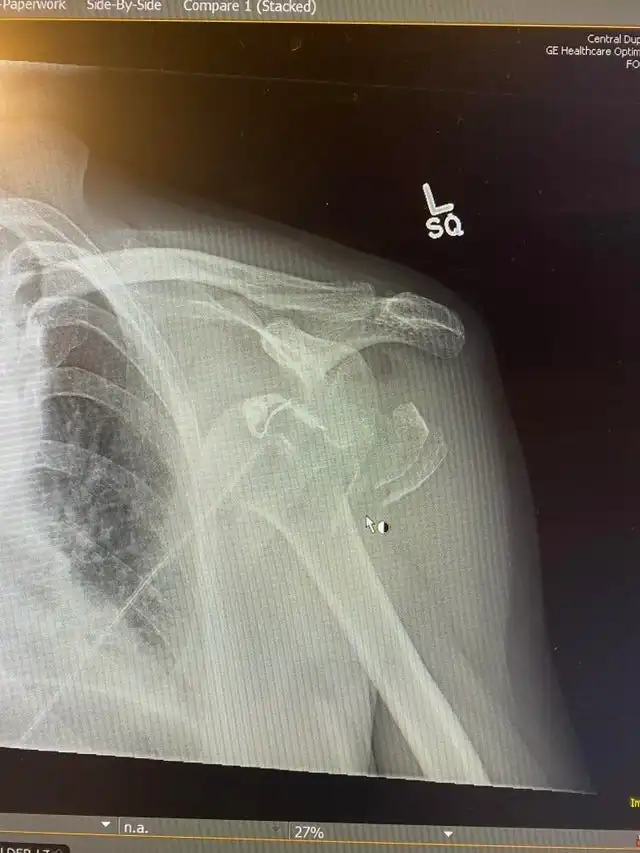

Так выглядит вывихнутое плечо

"Я упал в прошлую пятницу"